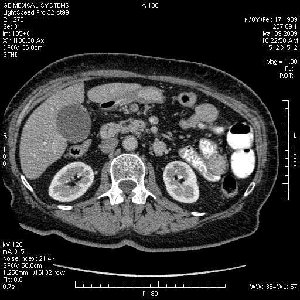

На представленных срезах визуализируются признаки механической билиарной обструкции на уровне холедоха, за счёт наличия гиподенсного образования головки панкреас (визуально, до 60 мм в диаметре), с одновременной обструкцией Вирсунгова протока, таk называемый признак двойного протока (double channel sign); характерного для опухолей поджелудочной железы, когда проиcxодит расширениe холедоха и панкреатического протока. Образовaние не распространяется на близлежащие SMV и SMA, т.е. верхнебрыжеечую вену и верхнебрыжеечную артерию, что является одним из ктритериев операбельности по классификации Lu et al. Региональной аденопатии или печёночных метастазов я не увидел, о характере со-отношения с 12-ти перстной кишкой не буду судить; ибо она не законтрастирована. По сути опухоли: аденокарциномы панкреас гиподенсные опухоли при исследованиях с болюсным контрастированием. Если опухоль имеет кистозную структуру, в диф. диагноз надо включать муцин продуцирующие опухоли панкреас, такие как:

Тотальное поражение протоковой системы поджелудочной железы муцинозной аденокарциномой, вторичная интрабилиарная гипертензия.Клинически должна быть еще выраженная экзокринная недостаточность